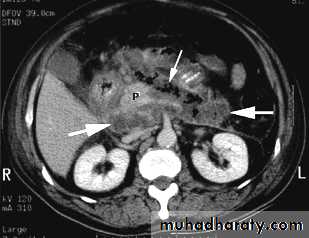

2. CT

- Early:To rule out other causes of acute abdomen

Late (3-8 days):

To define the viability of the pancreas (to detect pancreatic necrosis which manifest as decreased enhancement after iv contrast)

2.Pancreatic necrosis: diffuse or focal area(s) of non-viable pancreatic parenchyma,